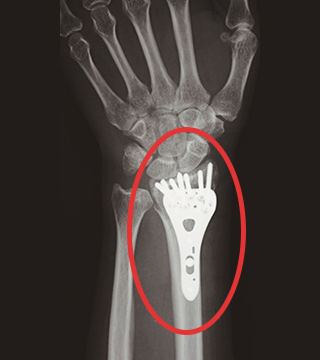

注目ポイント1 理想的な位置(関節の直下)にネジを入れ固定できる

ハイブリッドロッキングプレートを関節直下に固定しています。

1列目は強固に固定します。2列目は自由度があるため高い対応力を発揮します。